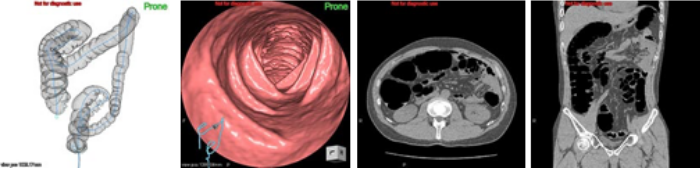

大腸CT

大腸の検査と言えば、これまでは内視鏡もしくは注腸と言われる大腸X線検査が主でした。しかし最近では大腸もCTで検査することができるようになりました。大腸CTは、大腸の中をあたかも内視鏡で見たかのような画像を得ることができます。またそれと同時に大腸X線検査のような画像、通常の腹部CTの画像も得られ、1回の検査で大腸だけでなく、腹部全体の画像診断を行うことができる検査であり、非常に有用です。ご希望の際は消化器内科にご相談ください。また大腸CTは大腸ドックとしても承っております。

検査について

精度は大腸カメラに劣りますが、比較的楽に大きい病変を見つけることができるといわれています(おしりからガスを入れるので個人差はあります)。また、お腹全体のCTをとるので他の臓器も同時に検査ができます。 内視鏡と比較して楽に受けられる検査だと言われています。以前大腸カメラをして辛かった方にはおすすめです。

検査の流れ

消化器内科外来または大腸ドックで予約をして頂きます。検査前日は腸に残りにくい食事と大腸CT用のバリウム製剤を摂取し、夜に下剤を内服し、当日午後から検査となります。お尻からチューブを入れ炭酸ガスを注入し、大腸を膨らませた状態で2回(場合によっては3回)CTを取ります。放射線の量は少なくして撮影しますので、以前の注腸検査よりも低被爆に行えると言われています。